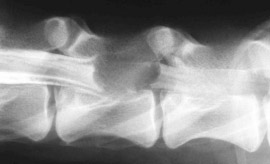

Enfermedad Discal Intervertebral Aguda: Claves en el Manejo Médico y Quirúrgico

El Diámetro del Canal vertebral como medida de la Gravedad de la Compresión Discal.

Mielografia & TAC & Resonancia Magnética: Maximizando el Diagnóstico por Imagen.